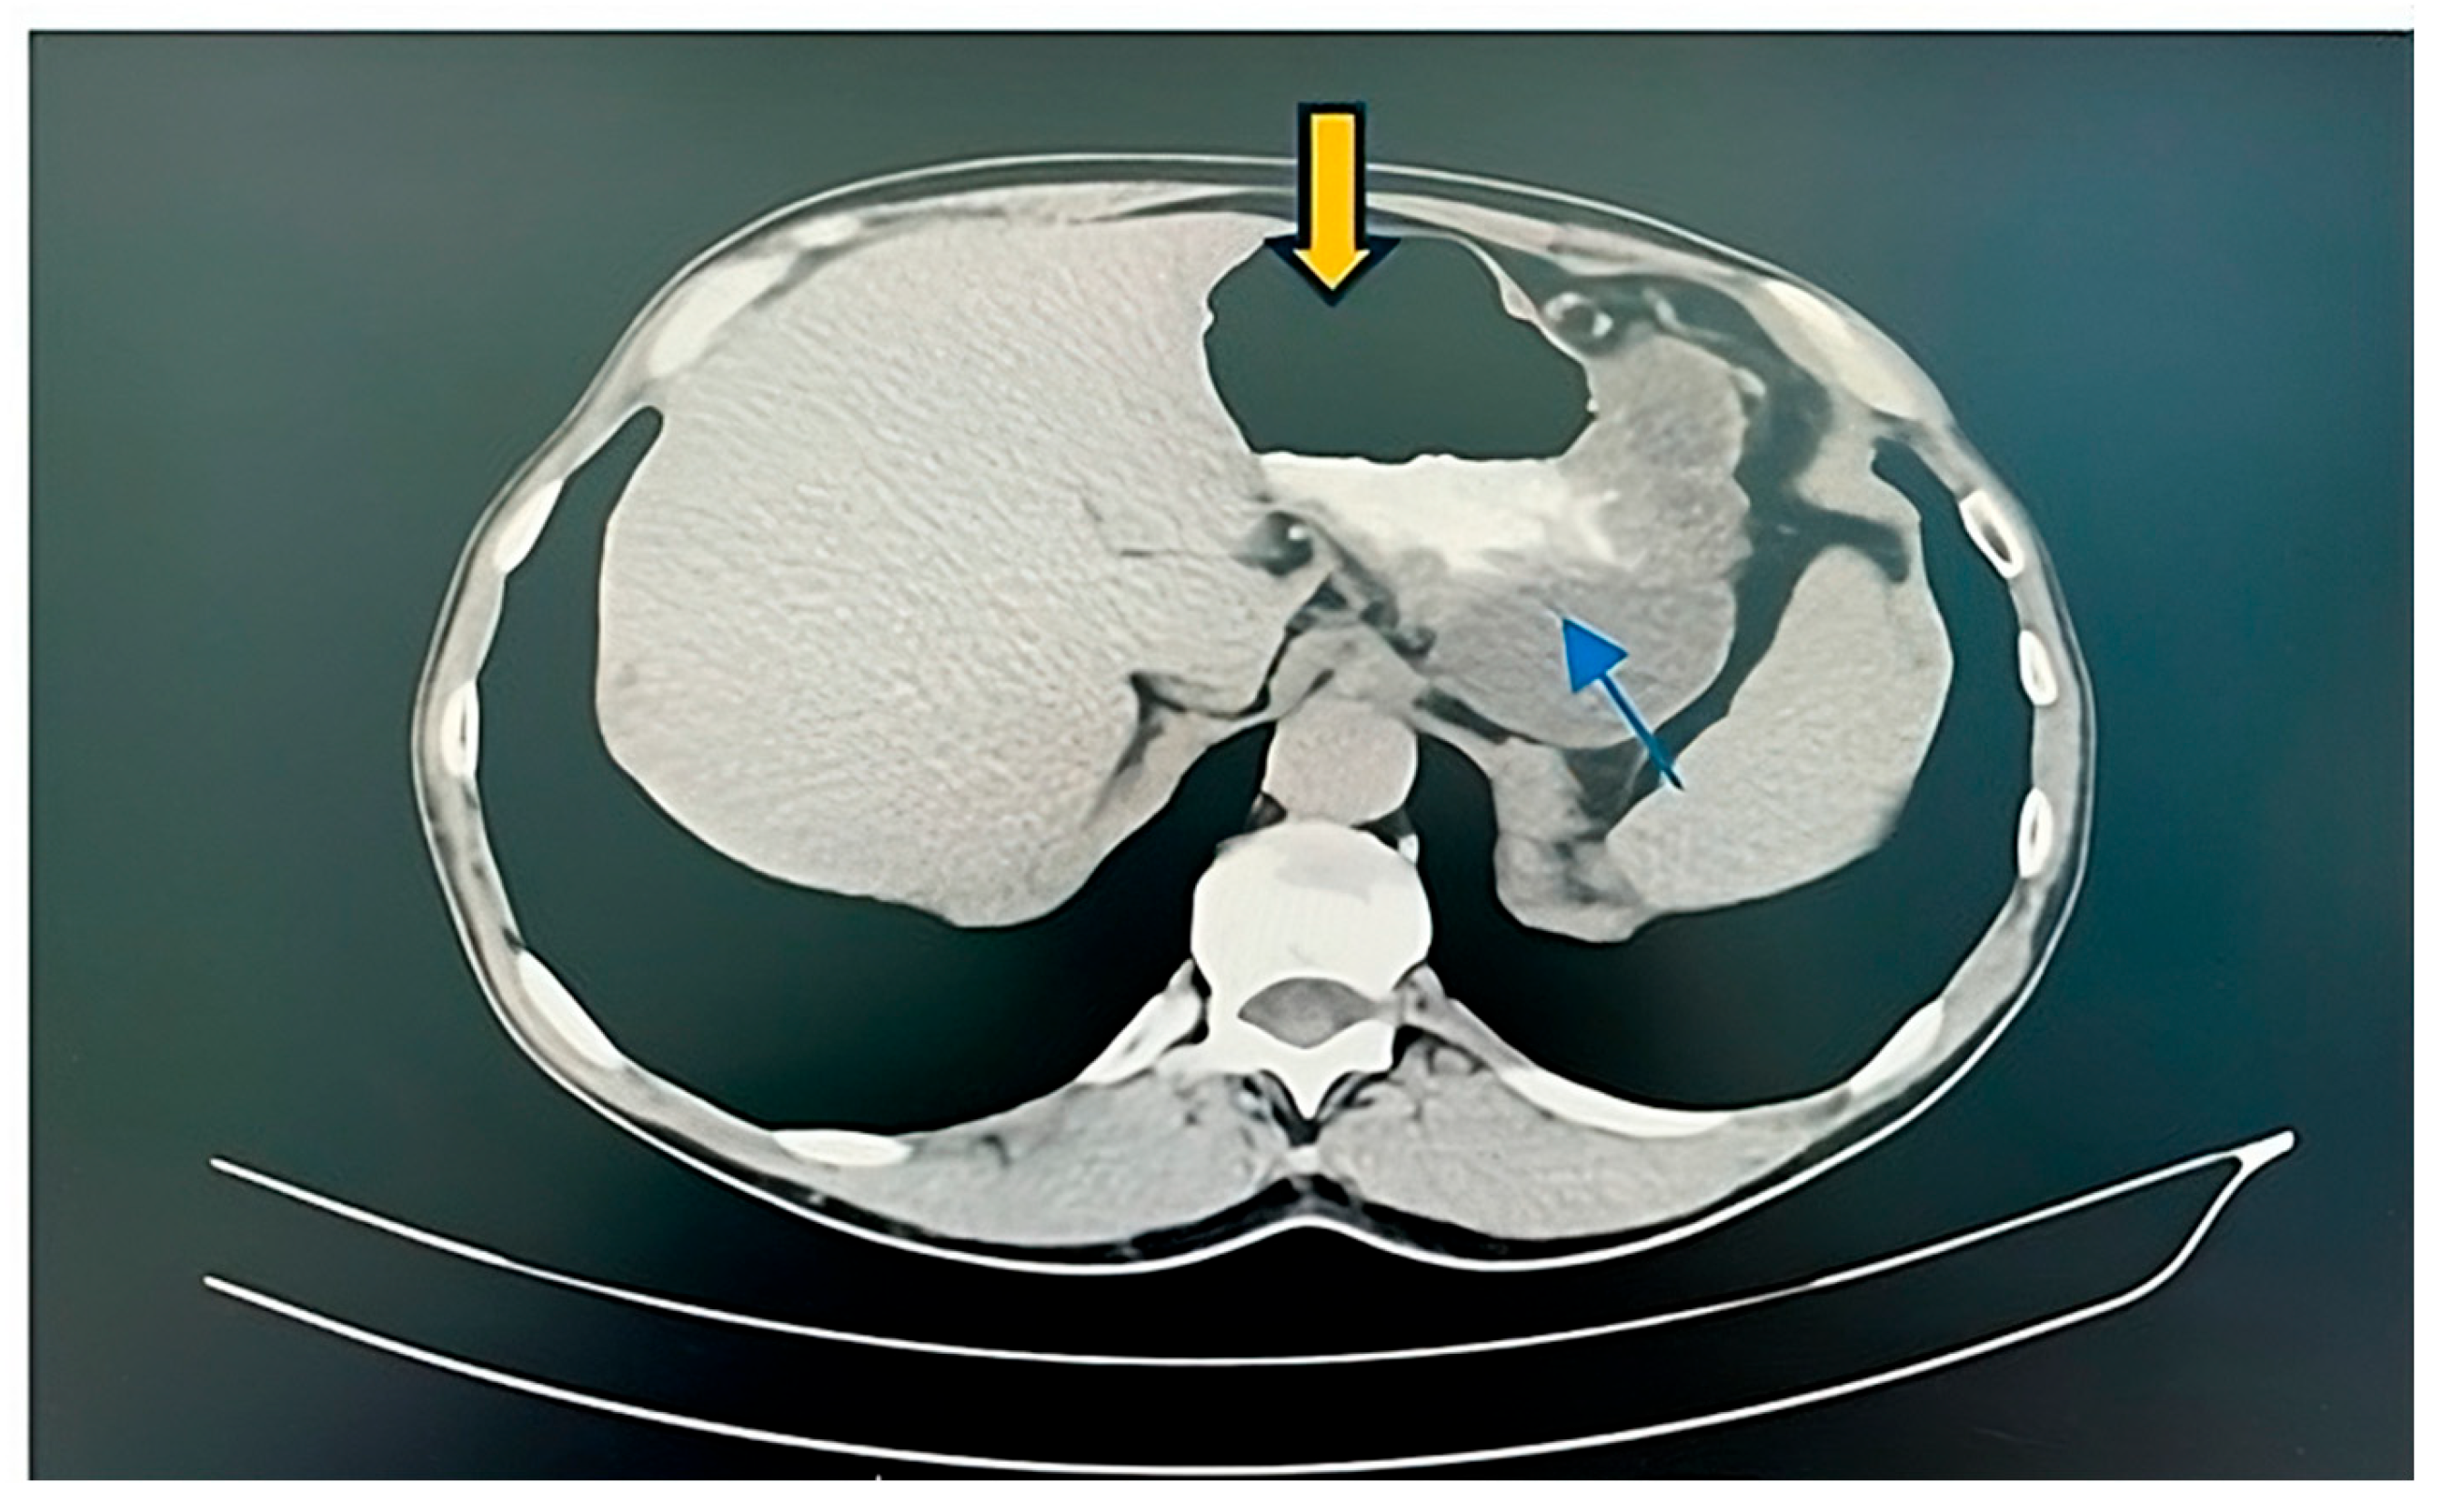

2. Case Report